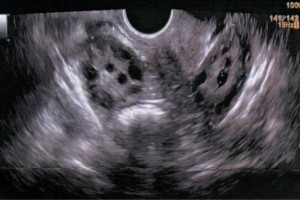

El programa fue diseñado para llevar de la mano al participante y ofrecerle herramientas que le permitan hacer una evaluación radiológica atinada, lo cual lo llevará a un diagnóstico que por ende arrojará el tratamiento idóneo. El énfasis se ha dado en la metodología diagnóstica, que es por inducción, así como el manejo del paciente, para crear una conciencia responsable y humana entre los que se dedican o quieren iniciarse en la práctica de la ultrasonografía. Dado a que existe una aplastante demanda de estudios de ultrasonido ante el insuficiente número de médicos radiólogos certificados, además de que el servicio de rayos x en México ha sufrido de ineficiencia en la aplicación del estudio y elaboración diagnóstica de la patología, la labor de este curso es formar de manera profesional a los médicos para que cubran y aminore en gran medida este problema que habita en el sector de salud.